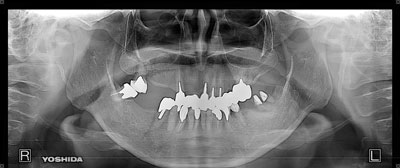

症例4【50代女性】左上6 副鼻腔膜を挙上しインプラント埋入 左上5 歯根破折の為インプラント埋入

治療前

左上5の歯根破折

治療後(10年経過)

主訴 左上奥歯で物が噛めない。入れ歯は煩わしいので、インプラントを希望。

左上第一大臼歯欠損部位は、骨の高さが3~4㎜しかなく、造骨の為にソケットリフト(骨造成)を行い、骨の高さを確保しインプラントを埋入。

約半年の免荷期間を経て、仮歯を装着、リハビリをし、約7ヶ月後にメタルボンド(金属焼付ポーセレン)を装着。

その後、左上第二小臼歯の歯根破折の為に、2本目のインプラントを埋入。(抜歯即時埋入)

リスクとしては、ソケットリフト(骨造成)による一過性の副鼻腔炎が起きる可能性がある。まれに洞底膜が破れる可能性がある。ただし、膜は約3週で再生するので、膜の回復を待ち、再オペを行う。

費用 111万(オペ。ソケットリフト・人工骨・採血による濃縮血小板生成・仮歯・最終補綴物まで含む)